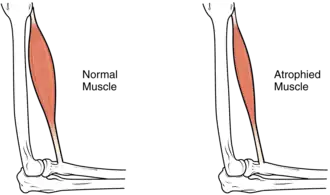

Muscle atrophy

In the long term, the loss of muscle function can have additional effects from disuse, including muscle atrophy. Immobility also can lead to pressure sores, particularly in bony areas, requiring precautions such as extra cushioning and turning in bed every two hours (in the acute setting) to relieve pressure.[52]

In the long term, people in wheelchairs must shift periodically to relieve pressure.[53] Another complication is pain, including nociceptive pain (indication of potential or actual tissue damage) and neuropathic pain, when nerves affected by damage convey erroneous pain signals in the absence of noxious stimuli.[54] Spasticity, the uncontrollable tensing of muscles below the level of injury, occurs in 65–78% of chronic SCI.[55] It results from lack of input from the brain that quells muscle responses to stretch reflexes.[56] It can be treated with drugs and physical therapy.[56] Spasticity increases the risk of contractures (shortening of muscles, tendons, or ligaments that result from lack of use of a limb); this problem can be prevented by moving the limb through its full range of motion multiple times a day.[57] Another problem lack of mobility can cause is loss of bone density and changes in bone structure.[58][59] Loss of bone density (bone demineralization), thought to be due to lack of input from weakened or paralysed muscles, can increase the risk of fractures.[60] Conversely, a poorly understood phenomenon is the overgrowth of bone tissue in soft tissue areas, called heterotopic ossification.[61] It occurs below the level of injury, possibly as a result of inflammation, and happens to a clinically significant extent in 27% of people.[61]